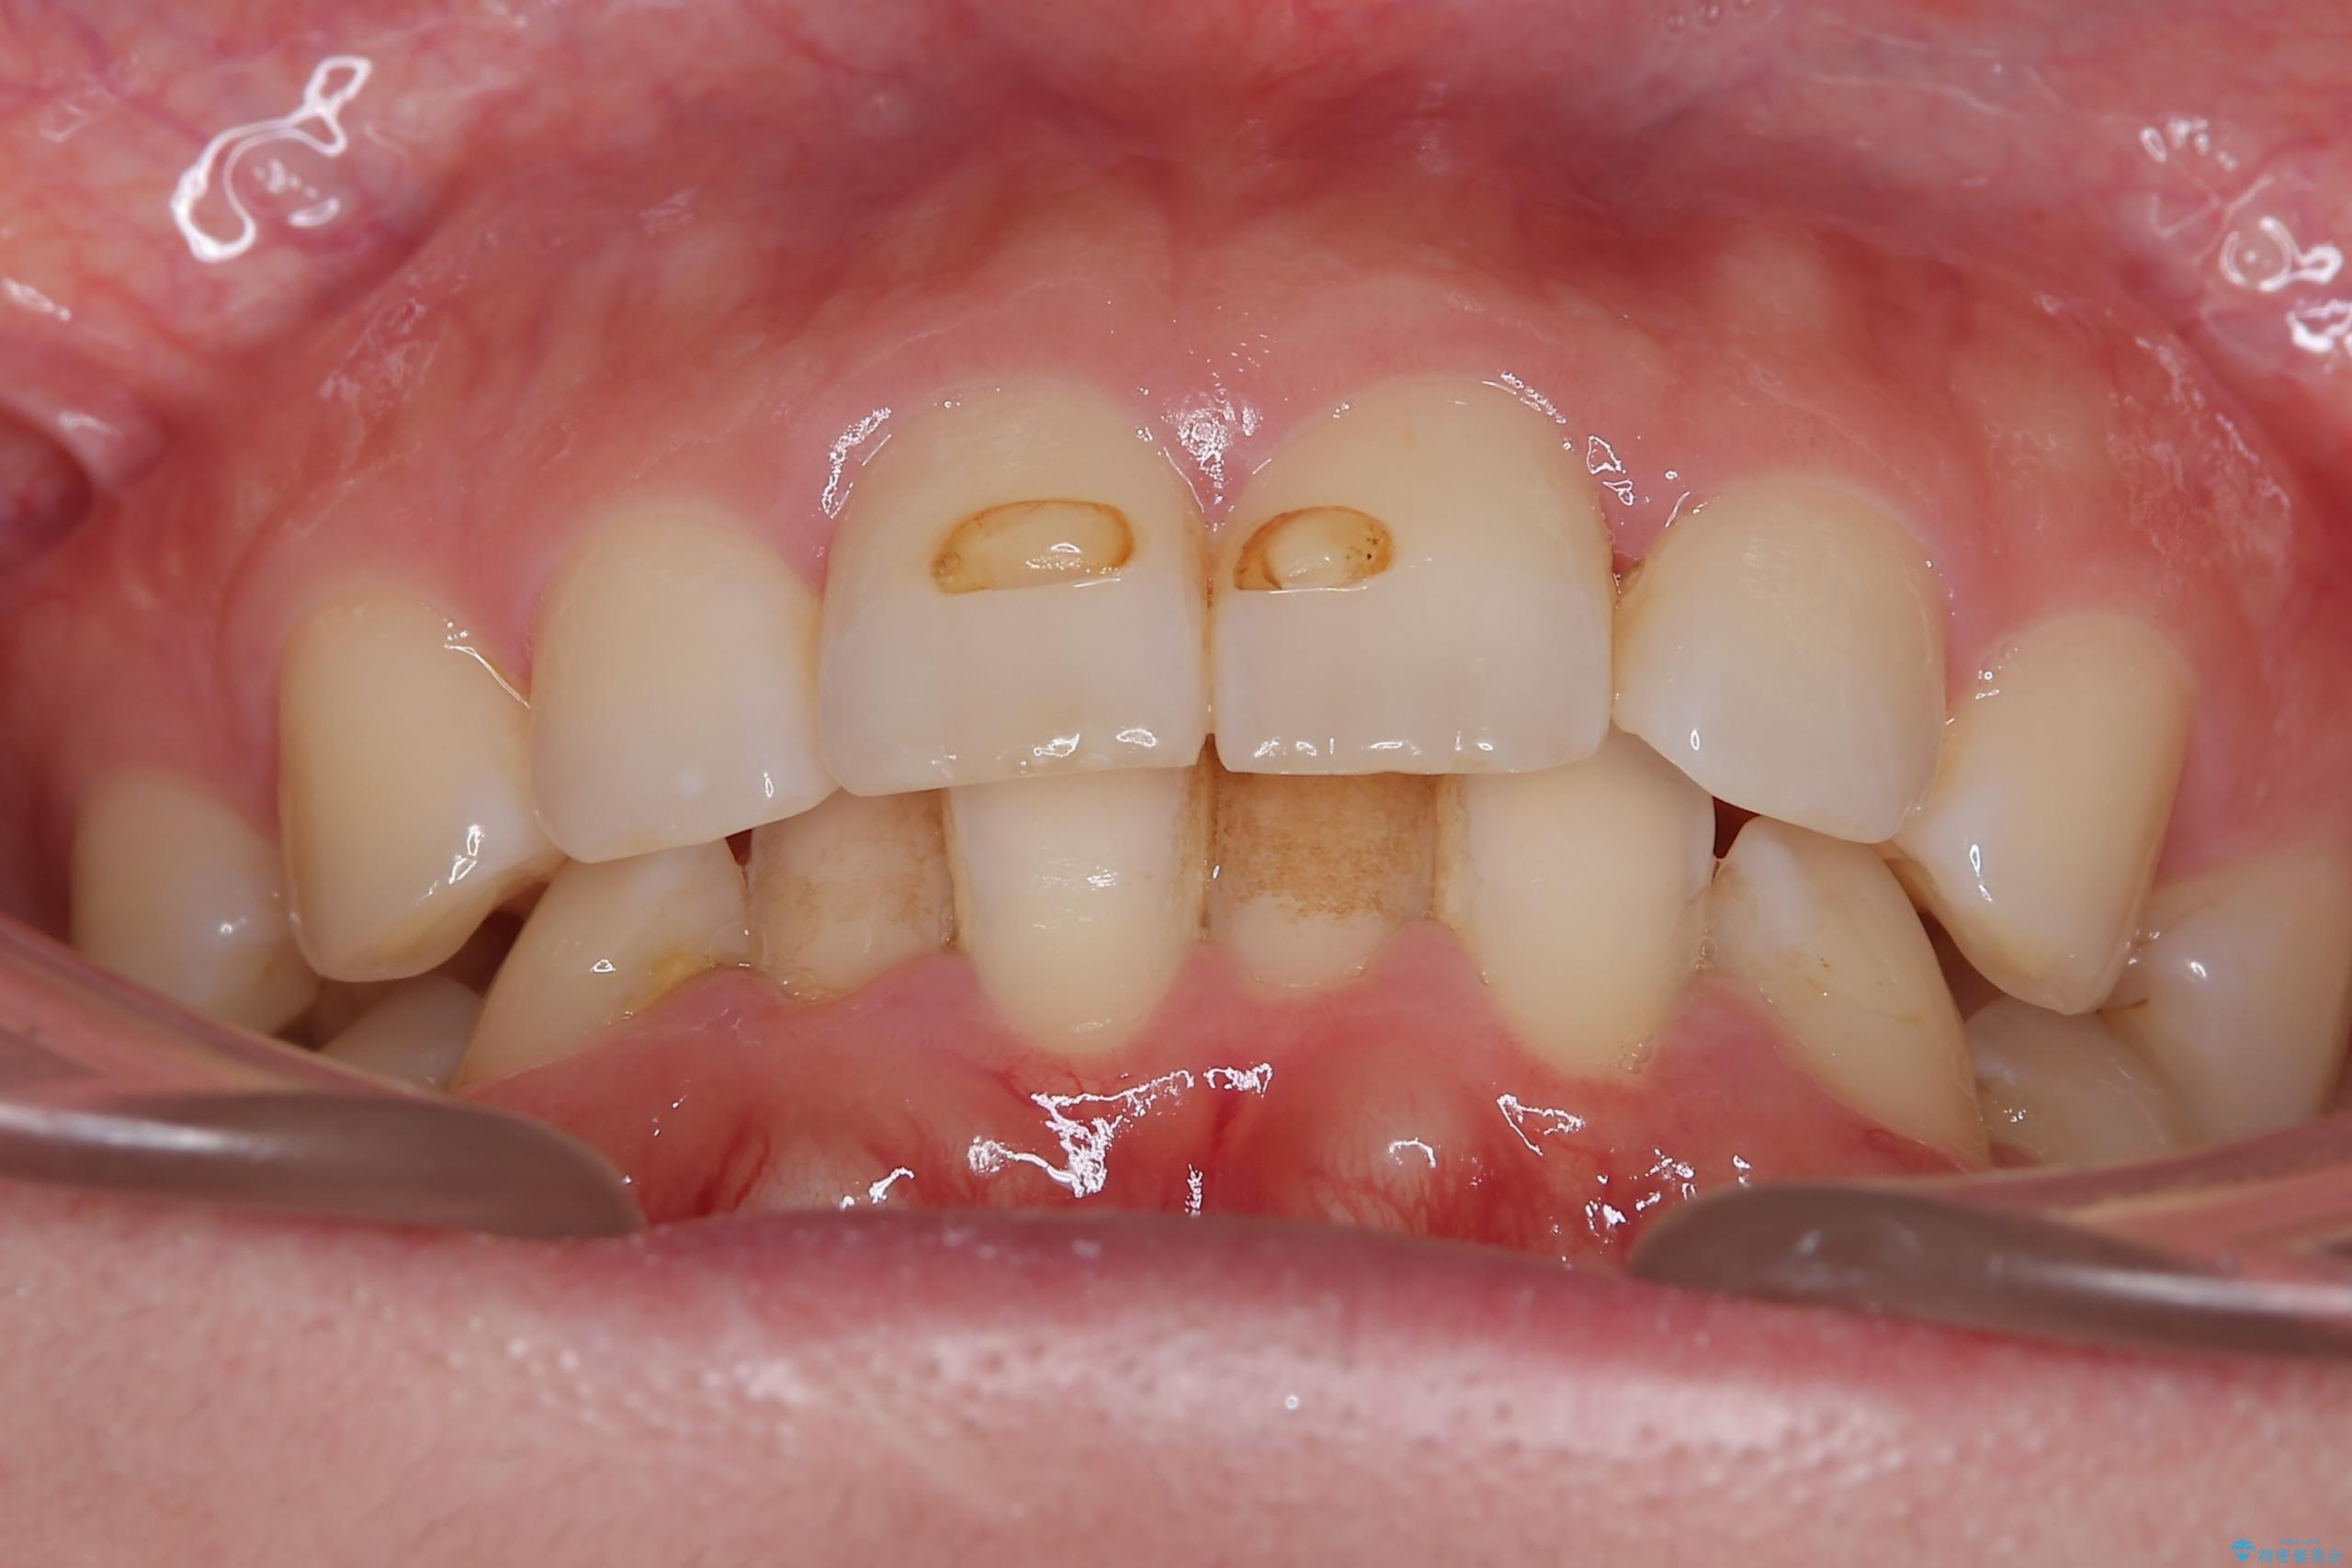

- 下の歯のがたつきを主訴に来院されました。

下の歯のがたつきと右の奥歯の噛みあわせ改善するために治療計画を立てることにしました。

噛み合わせをよくするために、ワイヤー矯正とインビザライン矯正のどちらの期間も必要な箇所にゴム掛けを行いながら治療を行いました。

下の前歯のがたつき改善にはIPR(歯と歯の間を削る処置)を行いました。

ゴム掛けを頑張っていただいたので、噛みあわせも改善され綺麗な歯並びになりました。